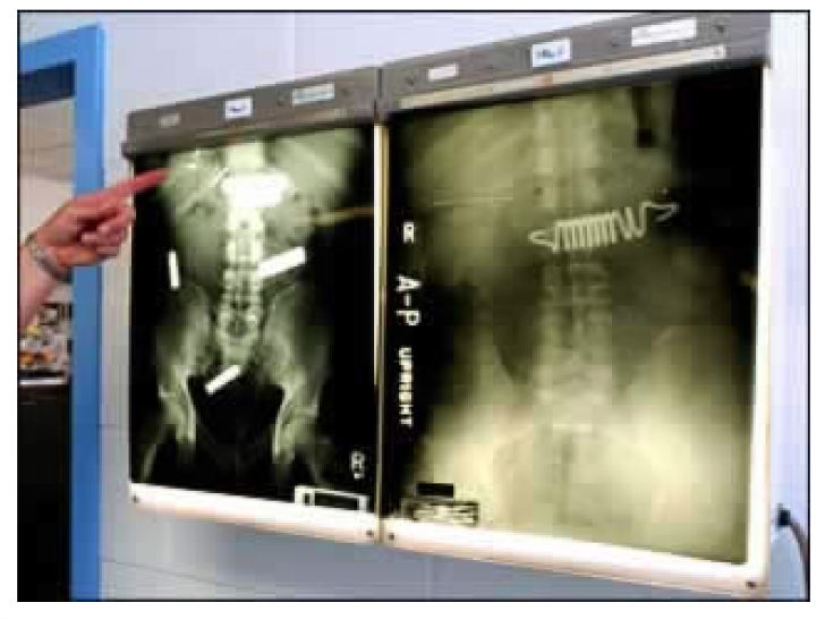

Some prisoners are ready to swallow anything to get out of prison, for example, to the hospital — even the springs from the mattress.